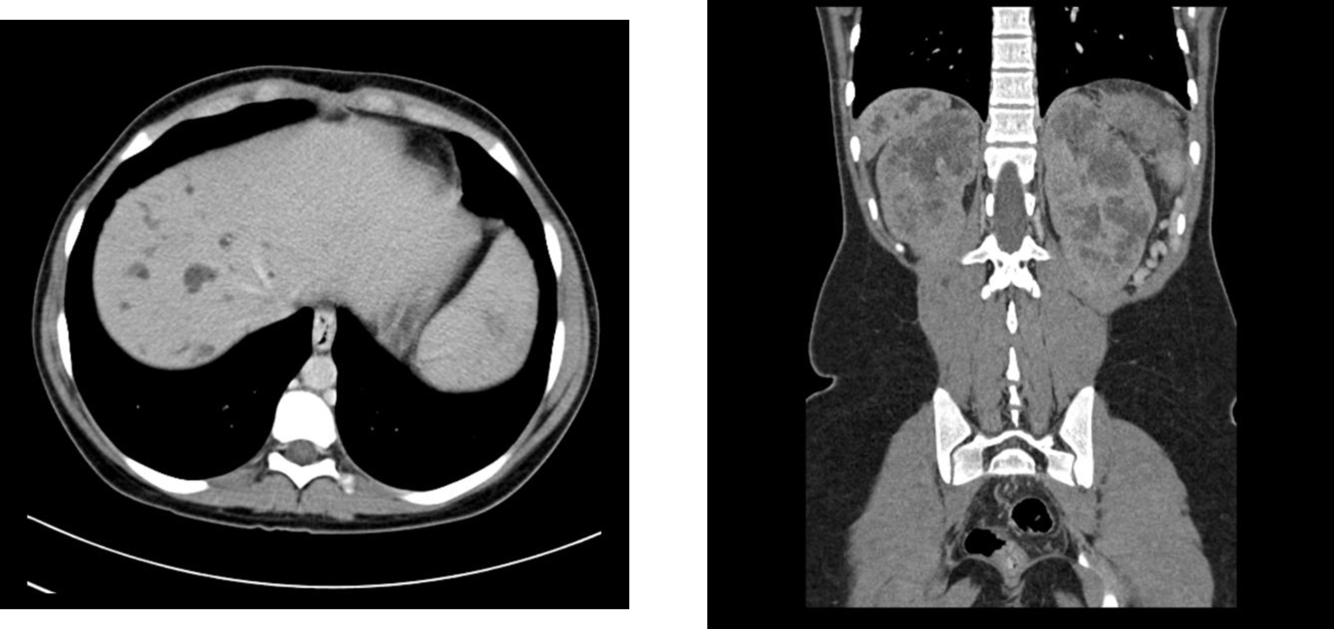

todani type IV

both extra and intra hepatic bile ducts

Caroli disease (todani type V) plus ADPKD

Caroli’s is associated with medullary sponge kidney and ADPKD and ARPKD

caroli disease (todani type V)